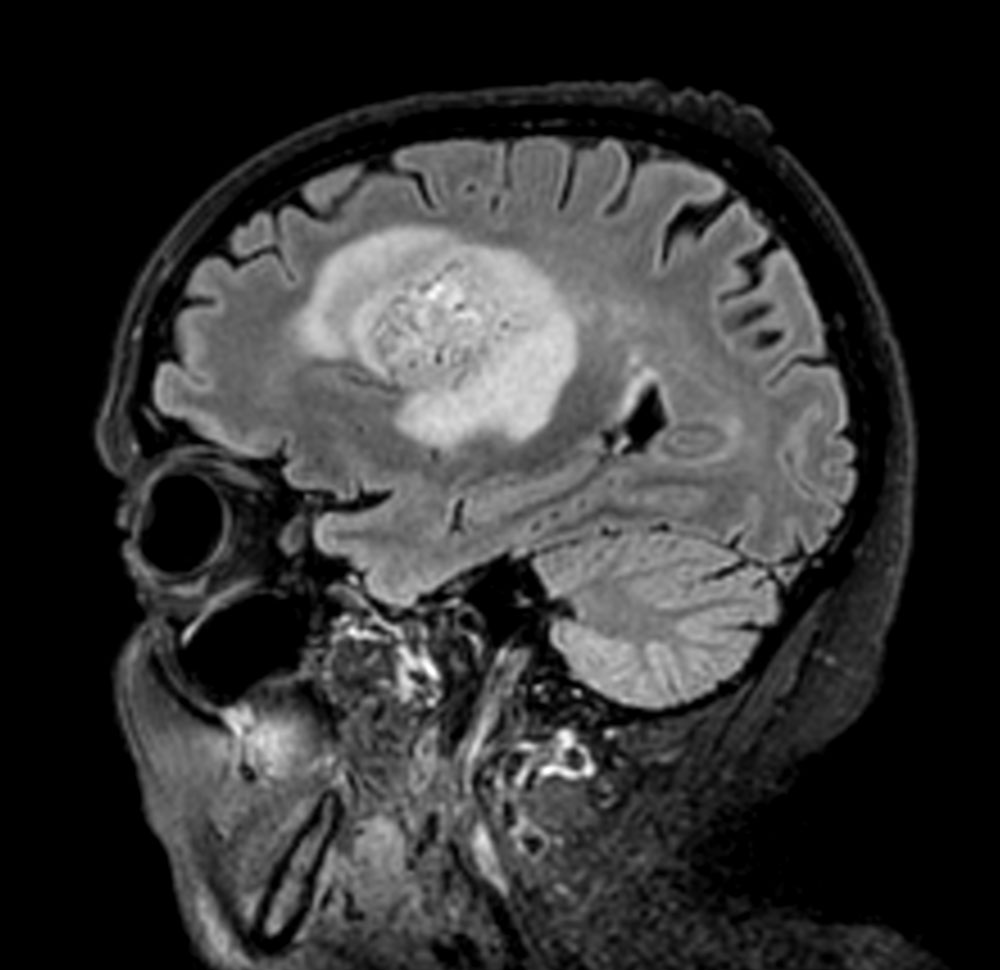

Sagittal T2w TSE

-